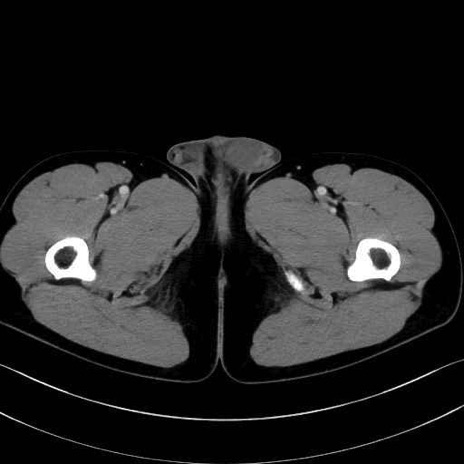

小殿筋(gluteus minimus)のCT画像の解剖

小殿筋 (Gluteus minimus)